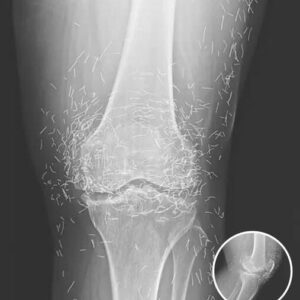

Unusual Joint Calcifications Reveal Rare Medical Condition

Doctors Stunned After Examining Unusual X-Ray of Woman with Persistent Joint Pain In a remarkable medical case that has both puzzled and fascinated healthcare professionals, a woman…